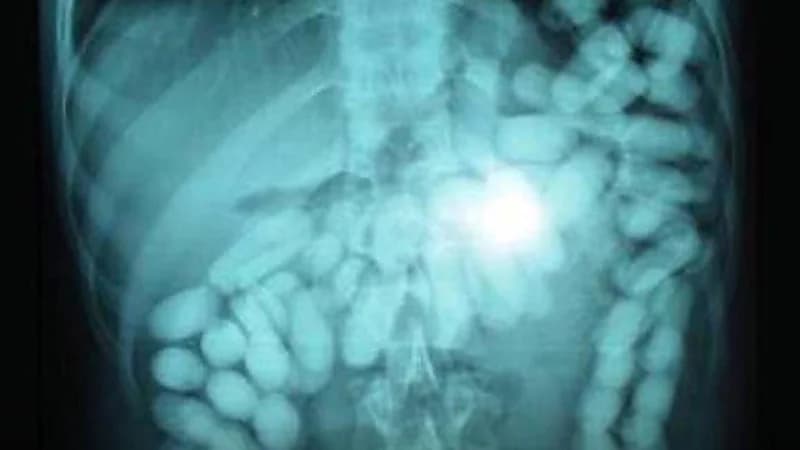

استطاعت مكافحة المخدرات بالأردن أن تستخرج من أمعاء مسافر في حدود المدورة المحاذي لحدود حالة عمار 6 بالونات تحتوي على (826) حبة كبتاجون مخدرة، كان قد ابتلعها ليتمكن من تهريبها إلى المملكة.

وبالتحقيق معه اعترف المتهم بإدخال حبوب المخدرات في أحشائه وعليه جرى اصطحابه إلى مستشفى معان الحكومي وبتصويره بالأشعة تبين وجود حبوب داخل أحشائه.

ويُشار إلى أنه تم إخراج ستة بلالين بداخلها (826) حبة من حبوب الكبتاجون المخدرة كان يحوزها بقصد توزيعها وترويجها على متعاطيها في المملكة .